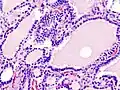

![]() | |

| Triiodothyronine (T3, pictured) and thyroxine (T4) are both forms of thyroid hormone. | |